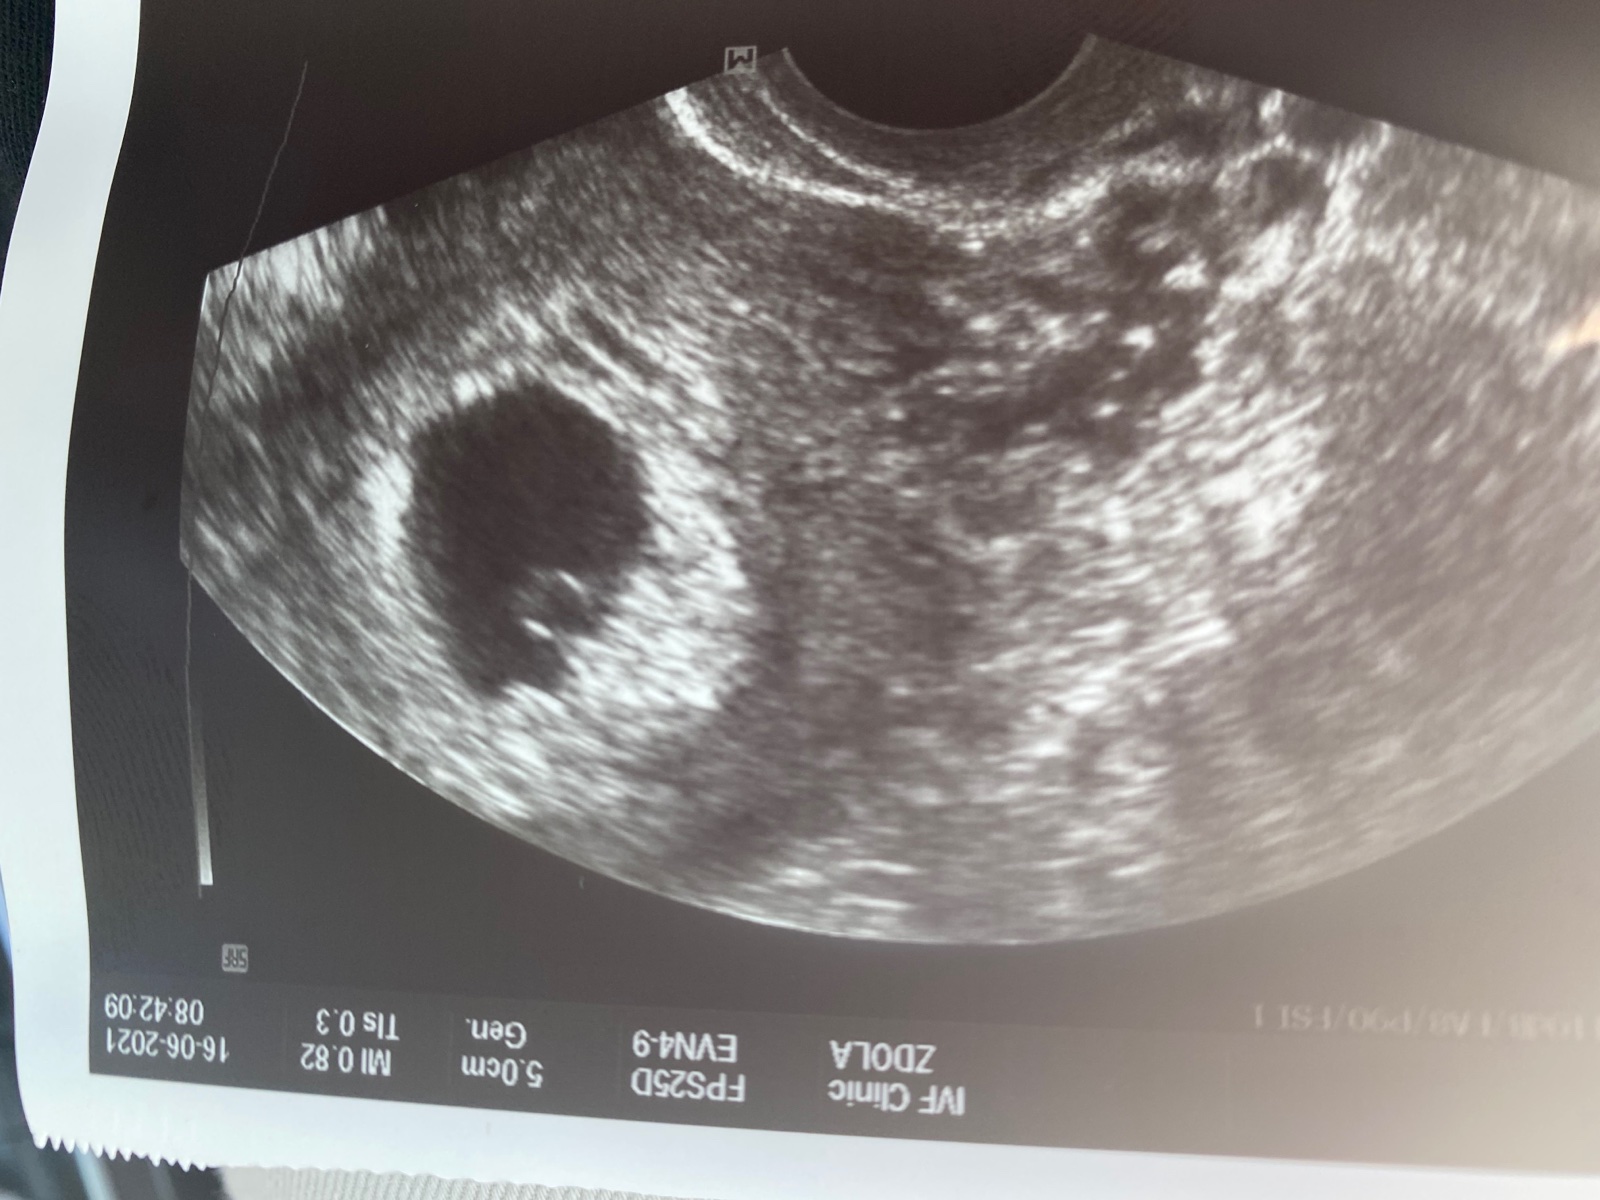

Otázka zni, otěhotněla některá přirozené a další tehu podstoupila ivf? Mame dvě oplodněná embryjka a zítra mě čeká transfer, přemýšlím zda zavést jedno nebo obe a jaká je šance ze to vyjde.veškerá vyšetření u nás dopadla Dobre.